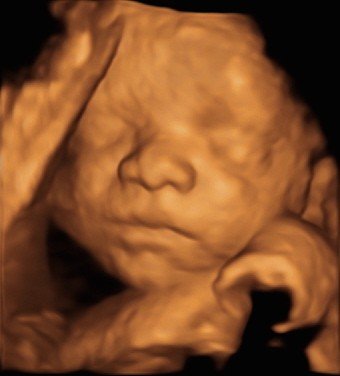

Baby scan image 4